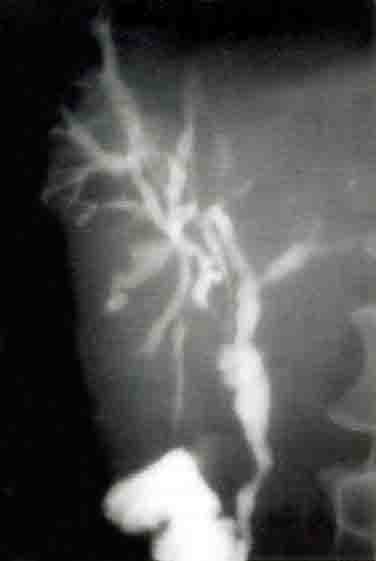

En revanche, l’IRM est surtout utile dans la recherche des signes en faveur d’une cholangite sclérosante compliquant une RCH en mettant en évidence une succession de sténoses et dilatations des voies biliaires. Cette technique est actuellement l’examen de base des voies biliaires, car elle permet d’obtenir une bonne cartographie des voies biliaires.

Figure n° 3 : Cholangite sclérosante après opacification

(Source hepatoweb.com)